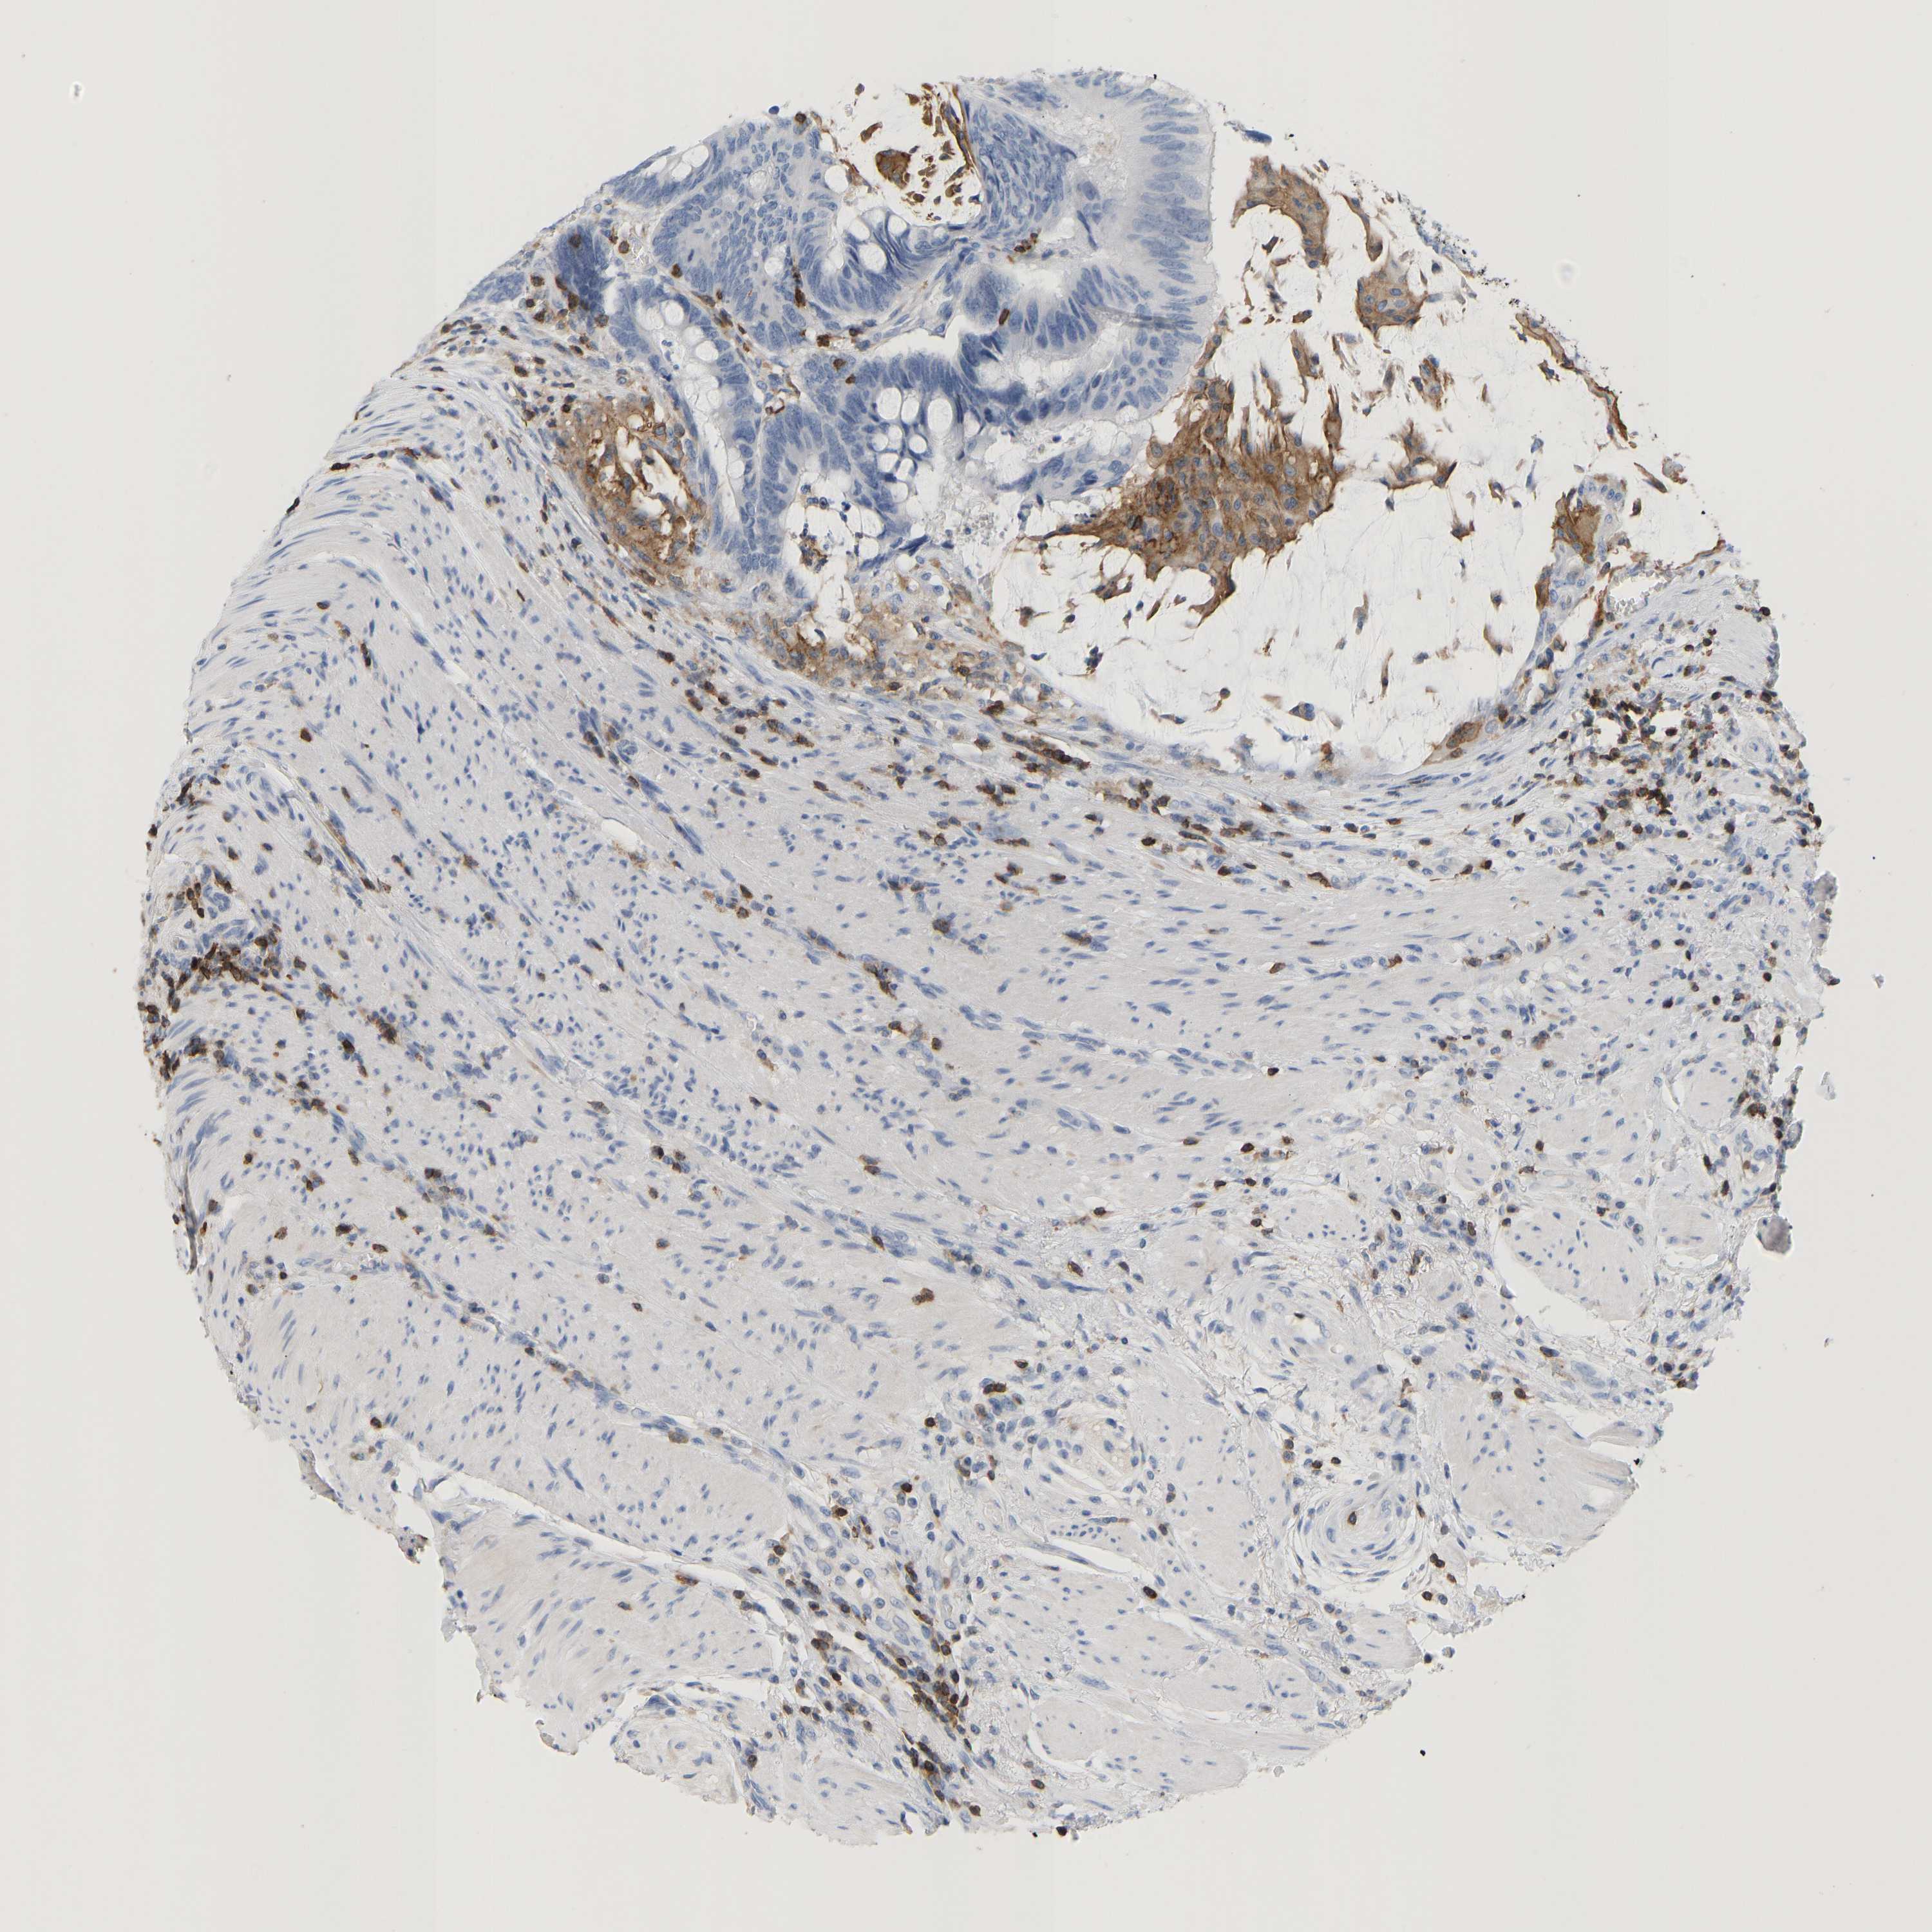

CANCER COLORECTAL CANCER Show tissue menu

COAD TCGA COAD VALIDATION READ TCGA READ VALIDATION PROTEIN COAD CPTAC PROTEIN EXPRESSION

ANTIBODIES

AND

VALIDATION